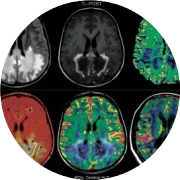

对M1上TMS引起的电场的仿真结果显示,电场集中在中央前回,平均峰值强度为87 V/m。关于小脑目标,引起的电场集中在右侧后叶的横裂周围,平均峰值强度为120 V/m,电场也涵盖了一些枕叶下部-后部区域(图3)。

图3. 对直径50毫米的“8”字形烙铁线圈(图1)诱导的电场(以V/m为单位)的仿真。

A. 对左M1进行个别RMT强度的TMS。

B. 对右小脑半球应用个别cbTMS强度的TMS。所有数据是基于8名受试者的平均值,投影到标准MNI大脑上。个体电场估计,请见补充材料(图S9)。